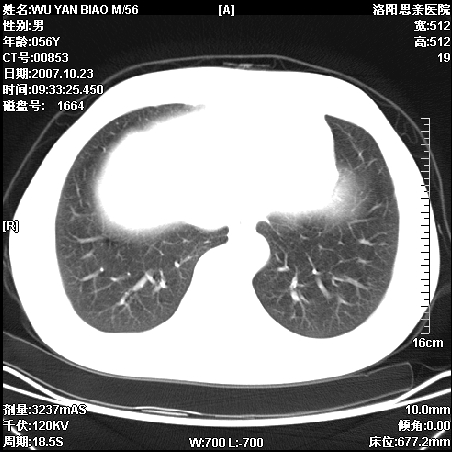

标题: CT10160:M56Y,体检发现,病人无不适,病人随访中 [打印本页]

标题: CT10160:M56Y,体检发现,病人无不适,病人随访中

后上纵隔占位,与肺交界清,宽基底附着脊柱,密度均匀,局部骨质无明确改变.

考虑;神经源性肿瘤,---起源交感n链?,不除外肠源性囊肿.

后纵隔神经原性肿瘤可能性大,孤立性胸膜间皮瘤待排.

支持后纵隔神经源性肿瘤!鉴别胸腔纤维瘤。